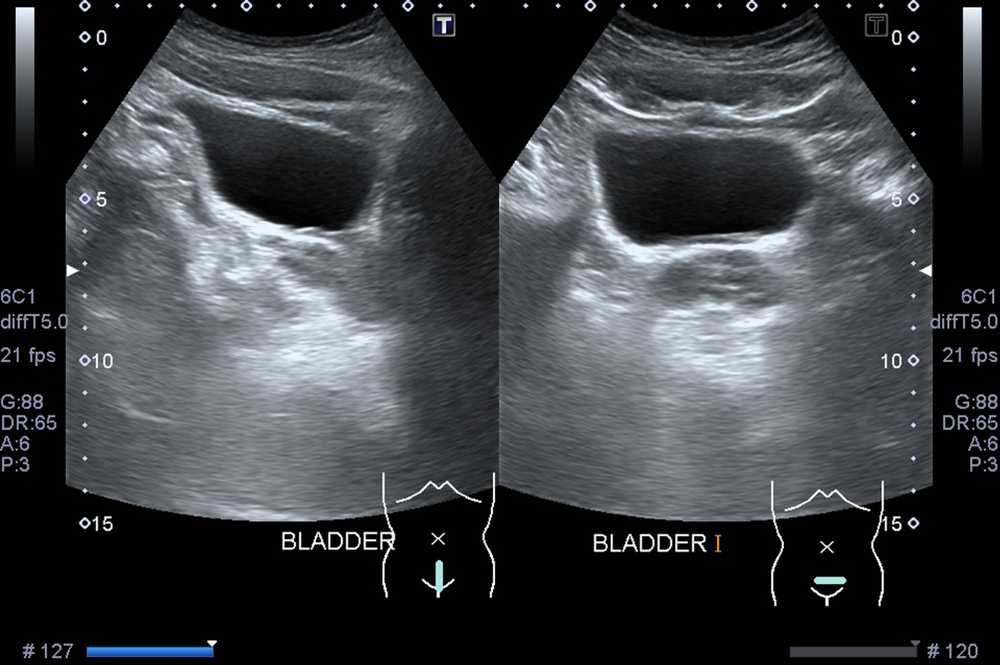

Трансабдоминальное УЗИ мочевого пузыря

это самый популярный способ. Он подходит как для мужчин, женщин (в том числе беременных), так и для детей.

Трансабдоминальное УЗИ мочевого пузыря выполняется через переднюю брюшную стенку с помощью наружного датчика.

Обязательным требованием к проведению обследования этим способом является наполненный мочевой пузырь. Диагностика позволяет оценить состояние мочевого пузыря в целом: определить его форму, размер, локализацию, строение и наличие патологий.